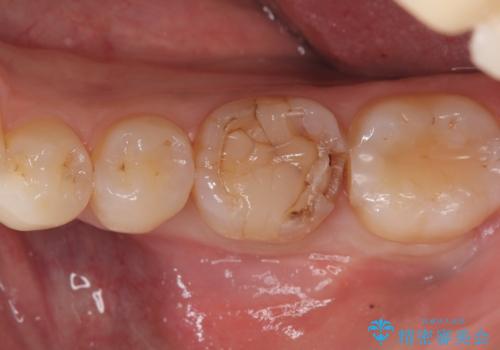

- 元々入っていたセラミックインレーは、6番目と7番目の歯の隙間を無理やり咬合面の近遠心的幅径を伸ばし埋めたような形態で、下部鼓形空隙が広めで食渣が溜まりやすい状態でした。

セラミックインレーを除去したところ、残存歯質が少なく破折のリスクを説明し、オールセラミッククラウン(スタンダード)でのやり替えとなりました。